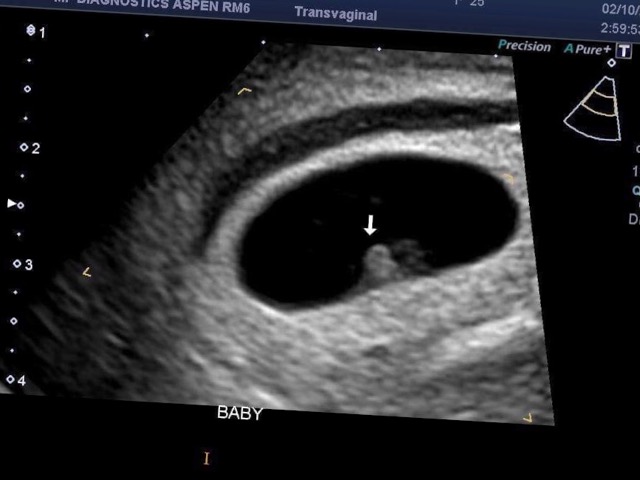

Ultrasound opinions? *pic*

My last period was August 1, I was assuming I would be about 9 weeks but when I went to my ultrasound today I was measuring 6 weeks 1 day so I’m so confused as to when I might have ovulated and conceived? I literally thought the baby would be bigger and not a tiny little blob hence the reason why I had a transvaginal ultrasound.